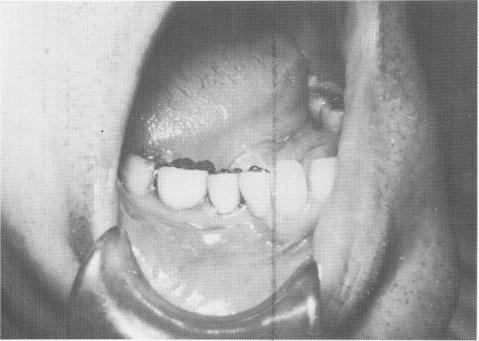

Far more effective than stabilizing with an inlay is splinting the usually stronger distal tooth to the implant with a full crown restoration. The case used as an example is that of a 57-year-old man whose lower right second bicuspid was used as a single abutment for an implant replacement of his first bicuspid. The abutment tooth was prepared for a full crown restoration, and on the next visit a two-unit splint was fabricated, using one of the soft impression materials (Fig. 8-50). (If using copper tube impressions with a modeling compound, this would have been done two visits later.) The splint was tried in the mouth for proper gingival fit, con-tour, and occlusion (Fig. 8-51).

Fig. 8-50. A prepared mandibular second bicuspid tooth that will act in symbiosis with a vent-plant to support a two-unit splint is seen.

Fig. 8-51. The splint is fitted into proper position so that all necessary adjustments of occlusion, interproximal fit, and gingival adaptation can be accomplished prior to the insertion of the implant.

1 Splint fitted into position prior to single tooth implant insertion

2 Lower single tooth implant site transfer to tissue with pencil tracing

3 Lower tooth in symbiosis with vent-plant implant for two-unit splint